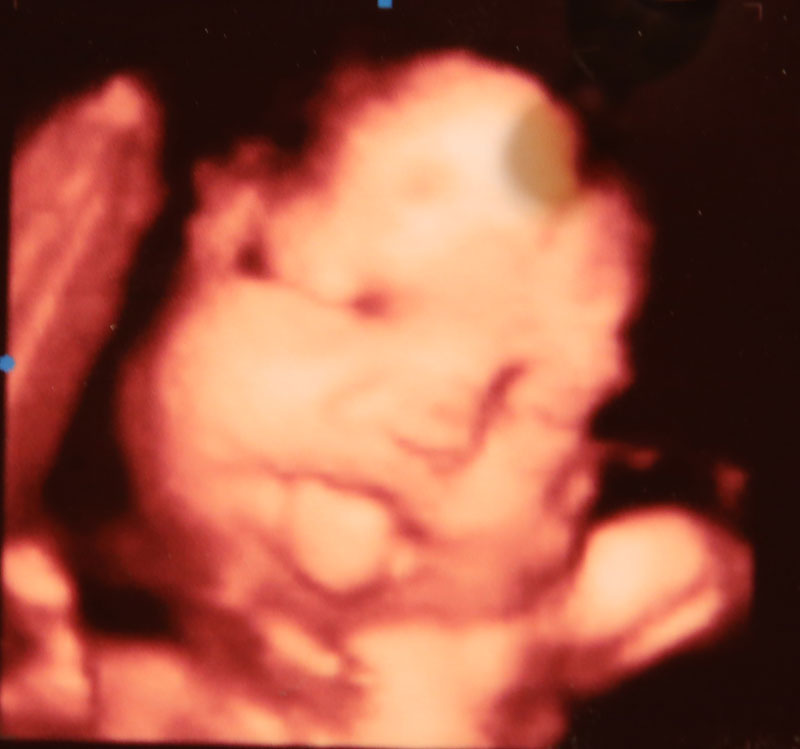

Raspberries and other facial expressions

Barberic, Burnett and Kemppel have seen facial expressions as early as 14 weeks.

“I’ve seen every kind of expression, from smiling and laughing to mad, crying looking,” Burnett said.

They’ve also all seen the tongue-out, raspberry-like facial expression.